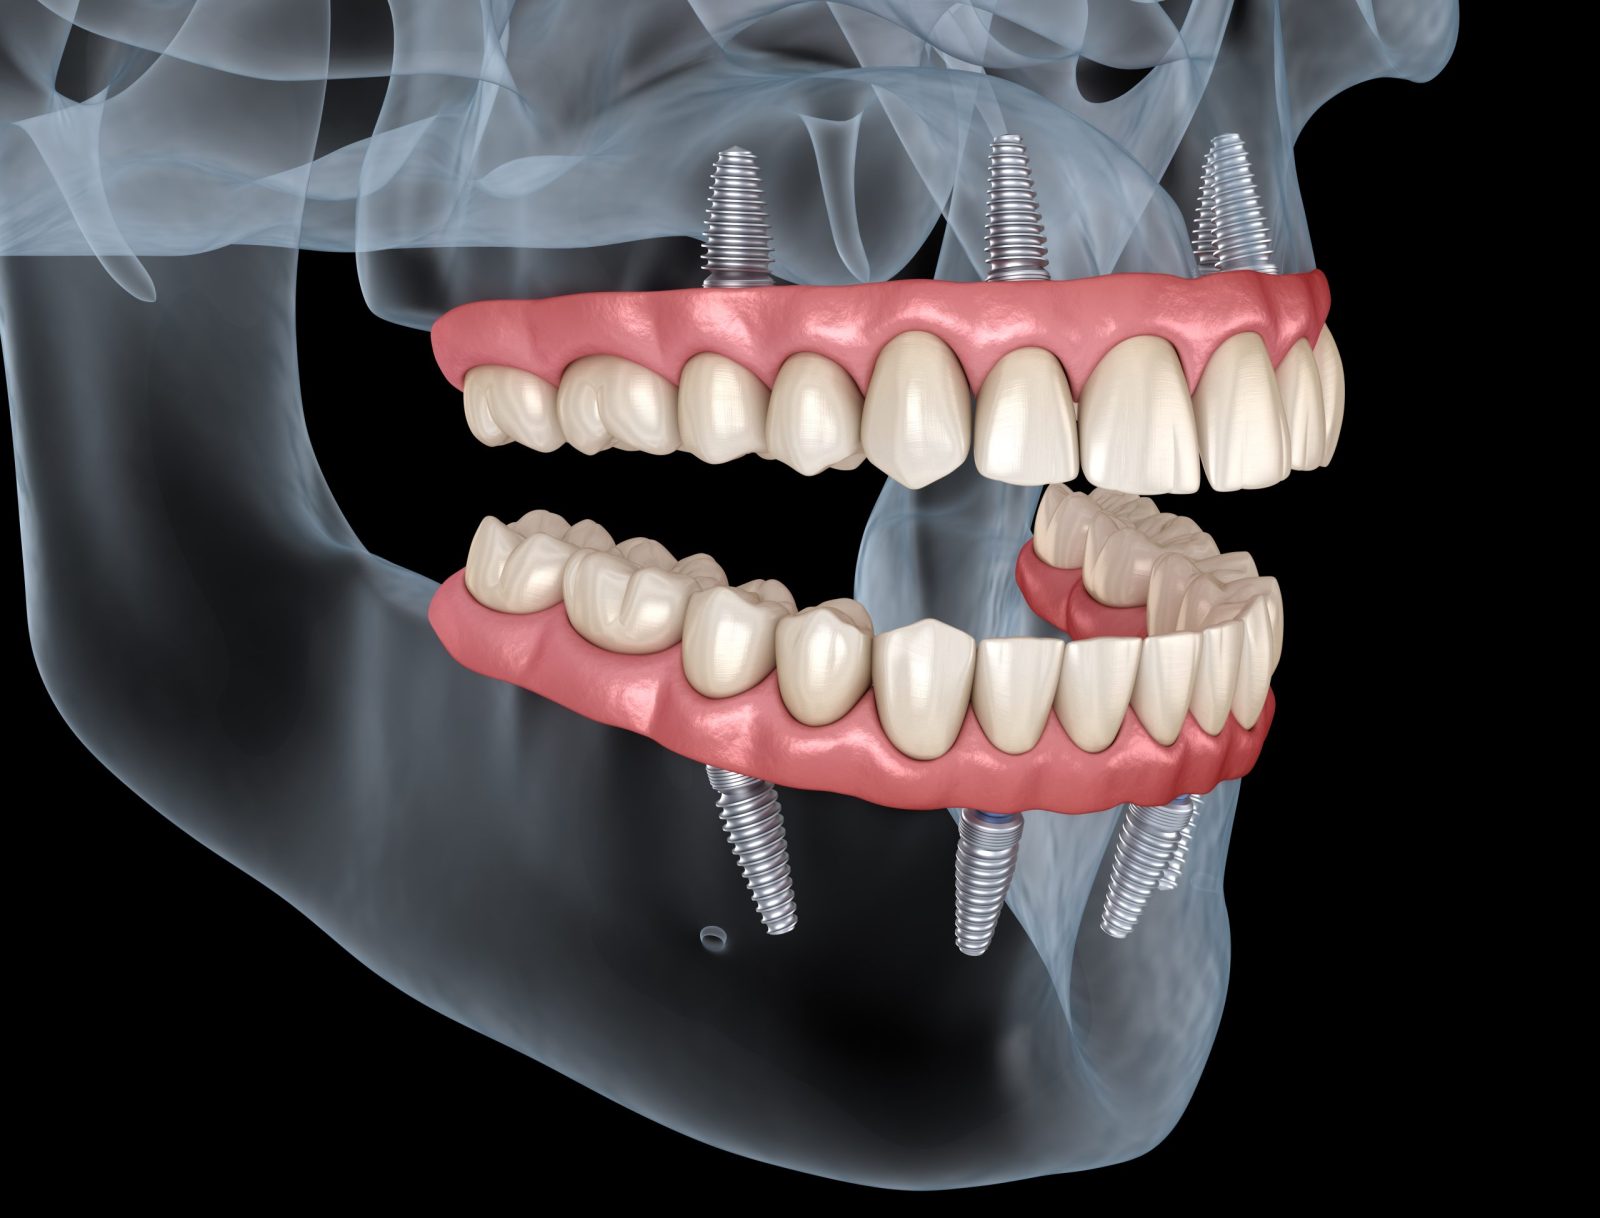

All on 4 dental implants cost is a significant consideration for many individuals exploring dental restoration options. This innovative procedure involves placing four strategically positioned implants in the jaw to support a full arch of teeth, offering a stable and long-lasting solution for those with missing teeth. The cost can vary based on several factors, including the materials used, the expertise of the dental professional, and the geographic location of the treatment facility.

Understanding the basics of All on 4 dental implants is crucial for anyone considering this option. The procedure is designed to provide a natural-looking and functional set of teeth, enhancing both aesthetics and oral health. For those interested in learning more about selecting the right provider, visit our page on Best All on 4 Dental Implants Near Me: How to Choose the Right Provider.

When considering the all on 4 dental implants cost, one of the primary factors to evaluate is the material used for the implants. Different materials can significantly impact the overall expense. Titanium is a popular choice due to its durability and compatibility with the human body, often resulting in a higher cost. On the other hand, zirconia is another material option that offers aesthetic benefits but may come at a different price point. Understanding these material differences is crucial when assessing the total cost of all on 4 dental implants.

The choice between titanium and zirconia can influence not only the all on 4 dental implants cost but also the long-term satisfaction with the procedure. Each material has its own set of advantages that can affect both the initial investment and future maintenance expenses. For those interested in exploring their options further, visiting a local provider can offer more personalized insights. To learn more about the all on 4 dental implants cost and available options, consider visiting our page on All-On-4 Implants Lake Hopatcong.